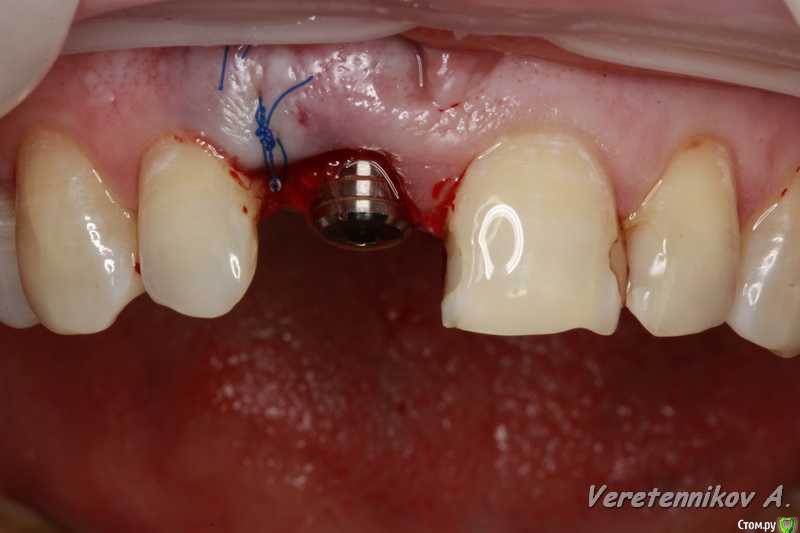

Популярный пост an_ver Опубликовано 15 января, 2016 Популярный пост Поделиться Опубликовано 15 января, 2016 11,жил долго и счастливо..но тут Новый год(((, скол ниже уровня ЦЭС на 3 мм...от экструзии отказалась.Из своего зуба сколхозил шаблон,чтоб наверняка. Удалил,кюретаж,вестибулярка целая, SPI 4.2*13 мм,с бугра ССТ,на всякий)),в щели Апатос,врем.абатмент,врем.коронка из своего зуба. 1ч.20мин.)) 27 Ссылка на комментарий

an_ver Опубликовано 16 января, 2016 Автор Поделиться Опубликовано 16 января, 2016 Клёво!!!Можно вопрос: как сст всовывали ?Просто опыта в этом аспекте очень мало и понятие "в щели" не совсем понятно.СпасибоВ щели: это свободные обьем лунки,после установки импланта,т.е. все пустоту забиваем графтом (Апатос). По ССТ: скальпель 15С, параллельно кости осторожно,маятниковыми движениями,до уровня прикрепления или глубже формируете карман,вкол с вестибулярки-выкол в лунке,вкол в сст,выкол там же,далее вкол внутри кармана и затягиваете сст...но проще посмотреть...сейчас А.Смолякова по рецессии выложила видео,принцип такой же 2 Ссылка на комментарий